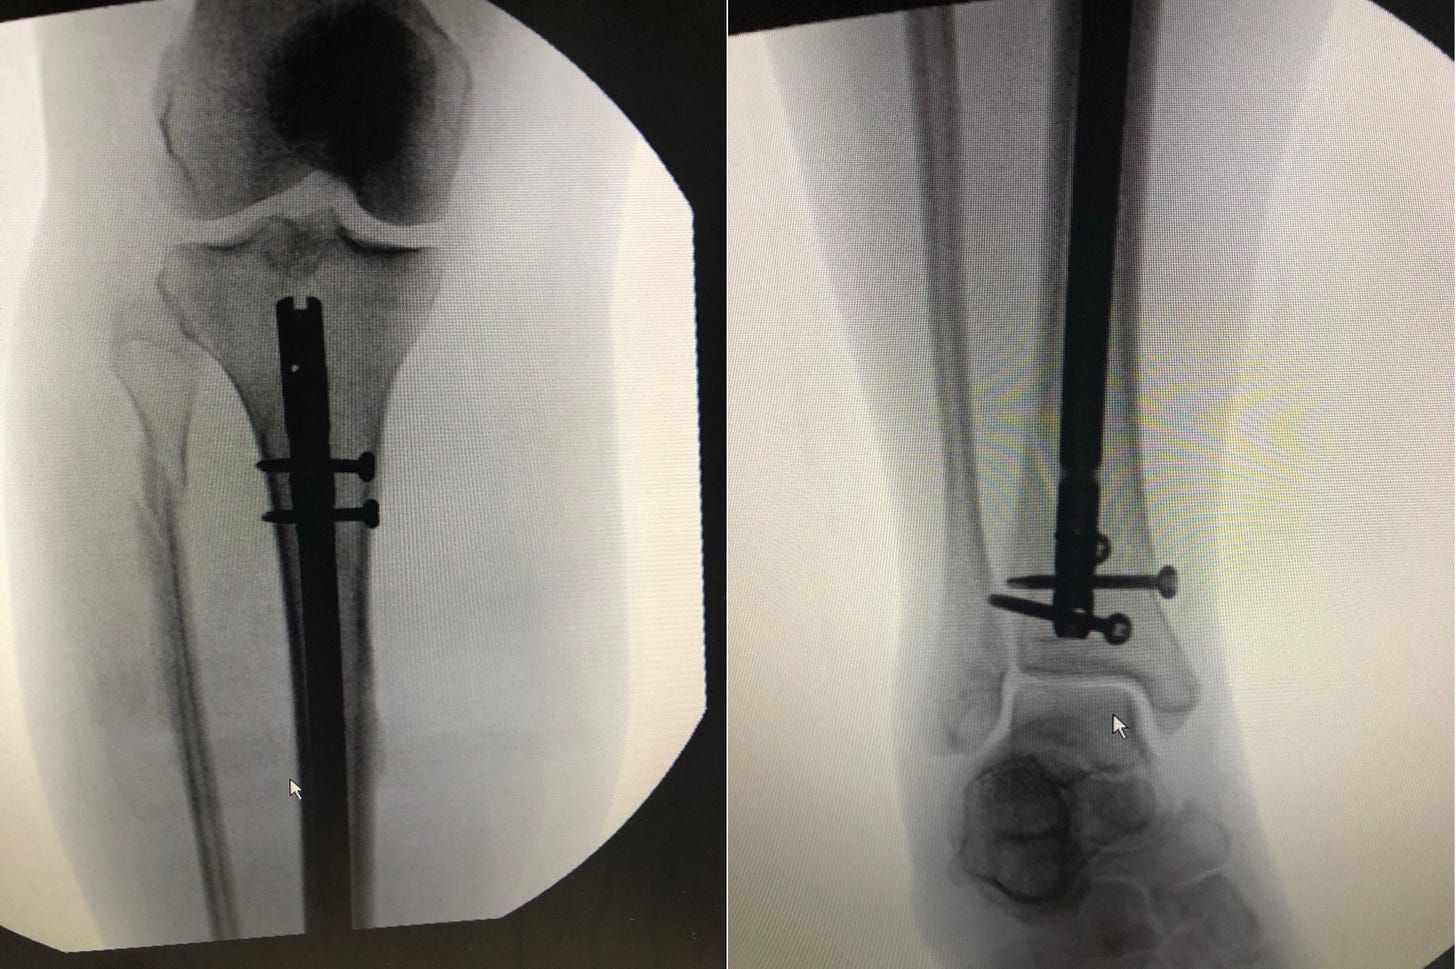

Finally, I was taken by ambulance to a Boston hospital for the surgery, and spent another three days in recovery before going home with a titanium rod and screws holding my bones together.

My fall was five years ago this week. Since then, I’ve had follow-up surgery to remove most of the screws. I walk without a limp, can dance and play pickleball.